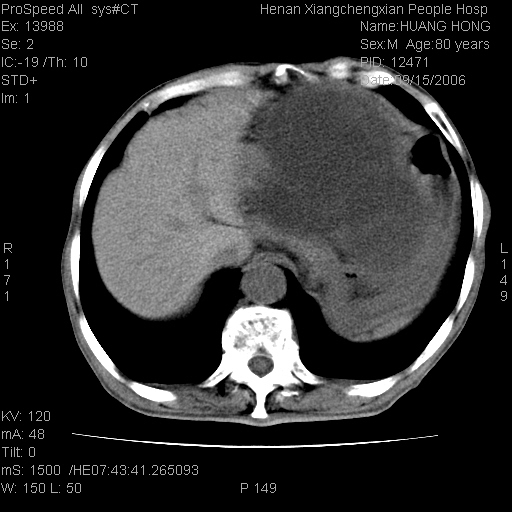

患者, 男, 80岁, 发现上腹部包块1年余,无其它不适.2006-9-14ct片是喝水后扫描2006-9-15ct片没喝水扫描![]() ![]() ![]() ![]() ![]() ![]() ![]() ![]() ![]() ![]() ![]() ![]() ![]() ![]() ![]() ![]() 以上是喝水片 以下是空腹片 ![]() ![]() ![]() ![]() ![]() ![]() ![]() ![]() ![]() ![]() ![]() ![]() ct:胰腺前方、肝脏与胃之间可见巨大类圆形囊性低密度影,大小约152mmx145mmx118mm,上缘平t11椎体上缘,下缘平l3椎体下缘,密度均匀,ct值15hu,其内呈多房分隔,囊壁薄且光滑,边界清晰,周围组织及器官明显受压。肝脏实质内未见异常密度影,胆囊未见异常,胰腺密度未见异常,脾脏大小、形态及密度未见异常,腹膜后间隙未见肿大淋巴结影。 印象:胰腺前方、肝脏与胃之间巨大类圆形囊性低密度影.性质待定。多考虑:.肠系膜巨大囊肿。 守望可可西里发言:支持楼主,考虑肠系膜囊肿,多为小肠系膜。 ysxyy发言:我总觉得这个病人虽然很像肠系膜囊肿,但还是应该强化一下; 下面这几幅图里肿块和主动脉的关系不太清,不知能否除外血管性来源? ![]() ![]() ![]() 病理结果:横结肠系膜间叶瘤.部分区域间质细胞增生活跃. 病理图片 ![]() 良性间叶瘤:是指由两种或两种以上的间叶组织所构成的混合性肿瘤.肿瘤仅发生在腹膜后和肠系膜,.前者较后者多发.良性间叶瘤常发生在肾或四肢,腹膜后较少见,各年龄均可发病.女多与男,预后较好,但术后易复法. 恶性间叶瘤:由两种以上恶性间叶组织成分组成. 光镜:肿瘤由脂肪/血管/平滑肌构成. 原贴地址: http://www.radinet.com.cn/forum_view.asp?forum_id=4&view_id=16217 ok |